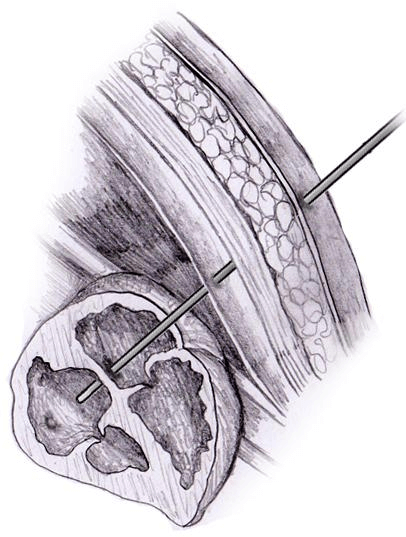

Η τροποποίηση των πρώιμων αυτών τεχνικών επέτρεψε από τότε τις επεμβάσεις με διαδερμική πρόσβαση και χρήση καθετήρων, και γνώρισε τεχνική επιτυχία όχι μόνο στη στένωση της εμβρυϊκής αορτικής βαλβίδας, αλλά και στην στένωση και ατρησία των βαλβίδων της πνευμονικής αρτηρίας, καθώς και στο σύνδρομο της υποπλαστικής αριστερής καρδιάς (HLHS) με άτρητο ή πολύ περιορισμένα ανοικτό μεσοκολπικό διάφραγμα. [13, 14]

Οι αναφορές για την κλινική πορεία των μωρών, που υπεβλήθησαν σε αυτές τις επεμβάσεις, όπως δίνονται από τις μεγαλύτερες σειρές αυτών των επεμβάσεων, επιβεβαιώνουν την τεχνική τους επιτυχία και την αναπαραγωγιμότητα. [15, 16] Υποδεικνύουν, επίσης, ότι οι επιτυχείς εμβρυϊκές επεμβάσεις οδηγούν σε βελτιωμένη λειτουργική ανάπτυξη των κοιλιών και του μυοκαρδίου, ενώ το έμβρυο παραμένει ακόμη στη μήτρα.

Άλλα επιστημονικά Κέντρα έχουν επίσης αναπαράγει τις αρχικές επιτυχίες [17,18], και τα στοιχεία που αποδεικνύουν ότι η βαλβιδοπλαστική του εμβρύου, που πάσχει από ατρησία ή στένωση των βαλβίδων της αορτής ή της πνευμονικής αρτηρίας, μπορεί να διευκολύνει την ικανότητα διεξαγωγής της κυκλοφορίας και από τις δύο κοιλίες μετά τη γέννηση, ενώ η διαφραγματοπλαστική για τα άτρητα ή με σοβαρό περιορισμό μεσοκολπικά διαφράγματα, μπορεί να βελτιώσει τη μεταγεννητική κυκλοφορική σταθερότητα και τις πιθανότητες επιβίωσης μετά την αρχική ανακουφιστική χειρουργική επέμβαση. [19, 20]

Θεωρείται, επίσης, πιθανό, ότι το ενδομήτριο περιβάλλον είναι εκ φύσεως ευνοϊκό για την επούλωση τραυμάτων και την αναγέννηση σε κυτταρικό επίπεδο. [21] Ωστόσο, πρέπει να καταβάλλεται μεγάλη προσπάθεια για τον κατάλληλο σχεδιασμό των επεμβάσεων και την επιλογή των υποψηφίων (τόσο μητέρων όσο και κυοφορούμενων παιδιών), ώστε να ελαχιστοποιηθούν οι πιθανές επιπλοκές και οι κίνδυνοι που συνδέονται με τις in utero επεμβάσεις.